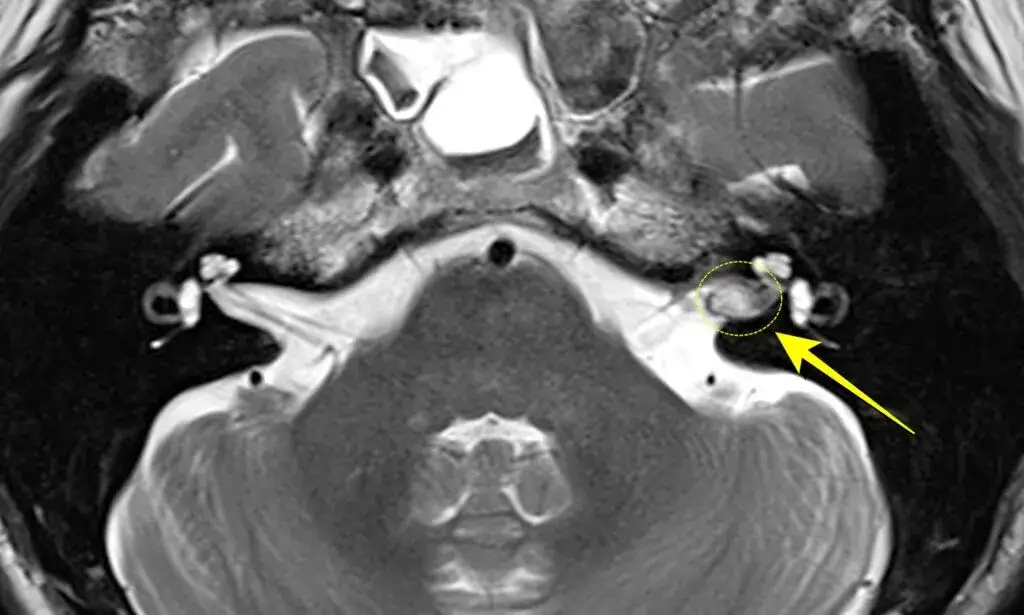

Rezonans magnetyczny (MRI) z kontrastem: złoty standard w potwierdzeniu diagnozy

Podstawowym i najbardziej precyzyjnym badaniem, które pozwala potwierdzić lub wykluczyć obecność nerwiaka nerwu słuchowego, jest rezonans magnetyczny (MRI) głowy z podaniem środka kontrastowego. Badanie to pozwala na dokładne zobrazowanie struktur mózgu i nerwów czaszkowych, uwidaczniając nawet niewielkie guzy. Jest ono uznawane za "złoty standard" w diagnostyce tego schorzenia.